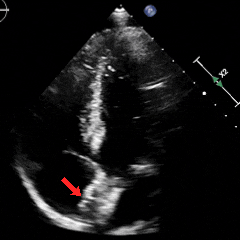

经胸右心声学造影:经左肘静脉注入震荡生理盐水(8mL生理盐水+1mL回抽静脉血+1mL空气经震荡制成),上腔、右房依次显影,造影剂完全充盈右心后,平静呼吸时,左房内即可探及微泡回声,约20-30个/切面/帧;瓦氏呼吸释放即刻,左房内探及微泡回声,不可计数。

术前静息状态经胸右心声学造影(中量)

术前瓦氏动作后经胸右心声学造影(大量)